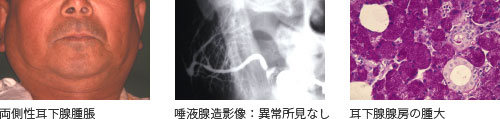

A唾液腺症

| 臨床症状: | 腺組織(耳下腺、顎下腺)の無痛性再発性腫脹、炎症所見は認められない |

| 検 査: | a)耳下腺造影:正常像、 b)血中アミラーゼの増加、 |